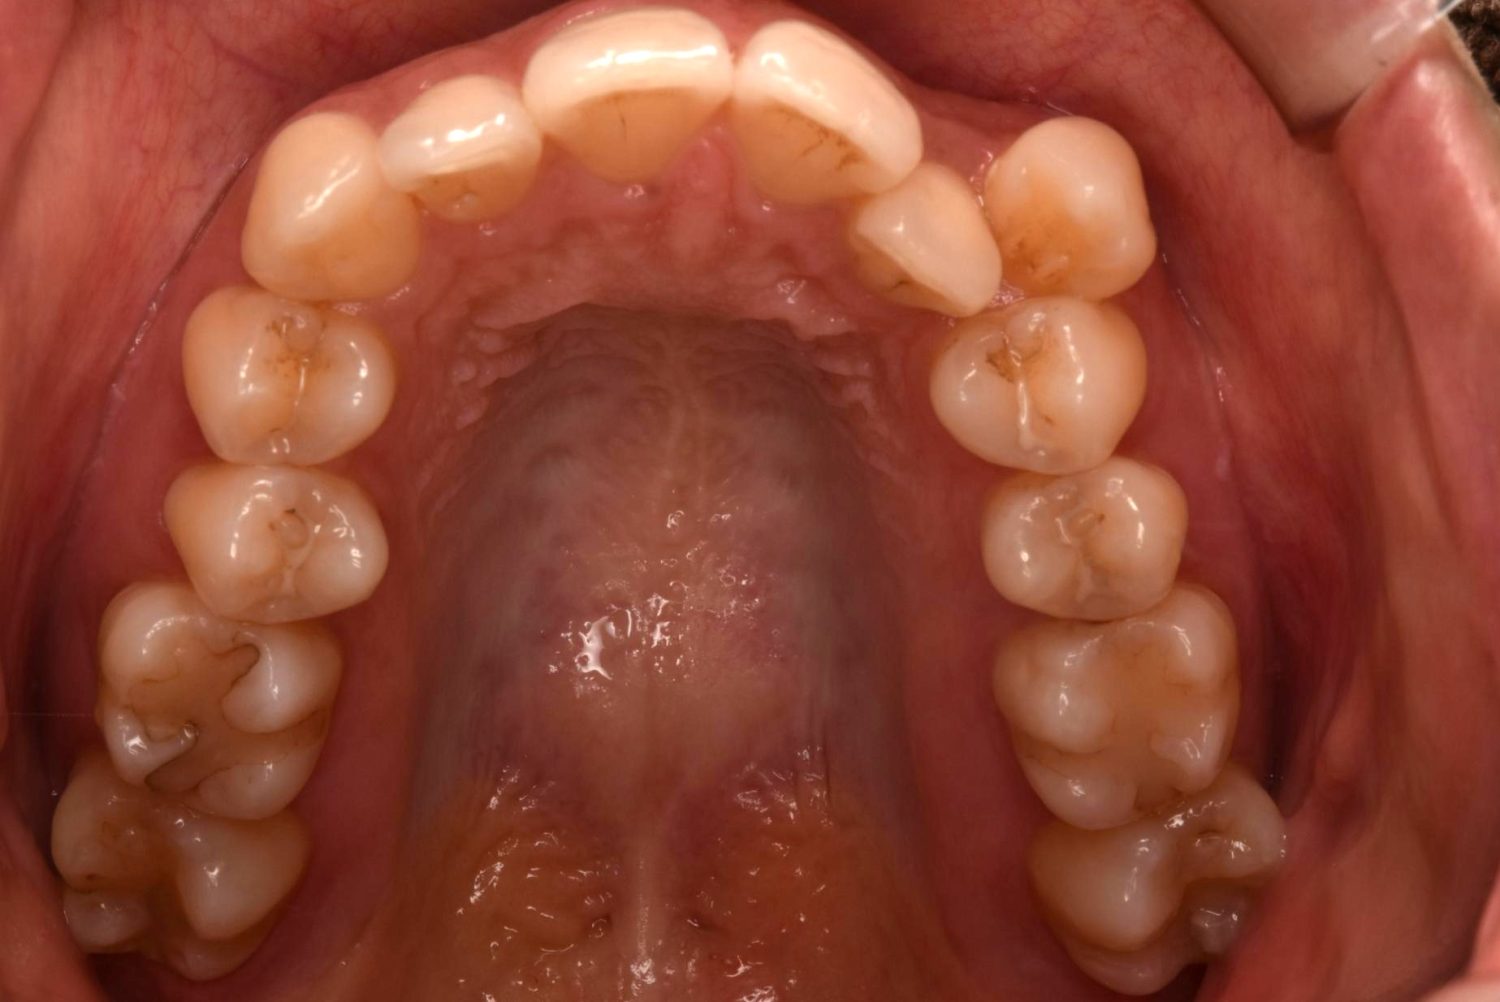

| 主訴 | 20代女性の患者さん。右上の八重歯が突出しており、前歯の見た目にコンプレックスを抱いていた。下顎の左右第2小臼歯(5番)が舌側に大きく傾斜しており、食事の際に、食べかすが詰まりやすく日常的に不快感を覚えていた。噛み合わせの改善と、見た目のバランスを整えたいという希望があり、矯正治療を行うことになった。また、目立ちにくい方法で治療を進めたいという意向から、マウスピース型装置の矯正 “インビザライン”を希望。 |

| 治療内容 | 下顎の左右第2小臼歯(5番)は舌側に大きく傾斜しており、矯正治療における歯の移動効率や全体の歯列バランスを考慮し、便宜抜歯を行った。また、上顎の左右第1小臼歯(4番)についてもスペース確保の目的で抜歯を実施し、全顎的な歯列の配列を円滑に進められるよう計画。矯正装置は、患者さんのなるべく目立ちにくい治療を行いたいという強い希望とライフスタイルに合わせて、マウスピース型矯正装置「インビザライン」(※1)を採用。抜歯が必要となる矯正治療は、診断・治療の難易度が高い方法である。当院ではCTやセファログラムなどの先進的な設備を完備し、多角的な診査診断と豊富な臨床経験をもつ理事長による治療を行うことで、このような難症例にも対応可能。 また、当院は矯正治療だけでなく、むし歯治療やクリーニングなどの一般歯科・予防治療も一貫して管理する包括的な審美治療を行う総合クリニック。治療中にむし歯などの問題が見つかっても、すぐに対応できるため、患者さんの通院の負担をできる限り抑えたスムーズな対応が可能。矯正専門医院ではできない包括的なサポート体制こそが、シャングリラデンタル横浜歯科矯正歯科で矯正治療を受けるメリットである。 矯正治療中は定期検診で経過の確認とクリーニングを行い、必要に応じて治療計画の見直しやマウスピース型装置の追加を行った。患者さんの高い装着遵守率も相まって、歯列は順調に整い、機能的にも審美的にも良好な結果をえることができた。 (※1)未承認医薬品等であるため医薬品副作用被害救済制度の対象とはならない可能性があります。 |